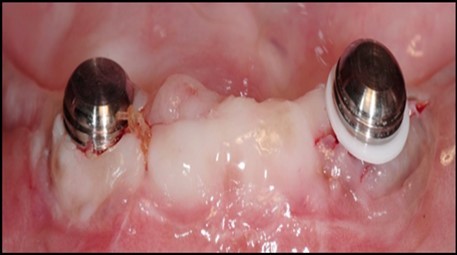

Post operatively after 3 months, osseointegration was evaluated clinically and radiographically (Figure 5a,b) and the implants were well prepared to receive the prosthesis. The second stage surgery was performed in which cover screws were removed and healing abutment were inserted into the implants (Figure 6). After a time period of two weeks, peri-implant soft tissue healing was examined, and existing denture was relined after relieving at the abutment site. Later, the healing abutment is removed using a 1.25 mm hex driver. Internal portion of the implant is irrigated and dried to make sure if it is free of debris and soft tissue. A periodontal probe was used to measure the gingival cuff height at the right and left canine site of implant location. Selected ball abutment were placed onto each implant using 1.25 mm hex driver and 30 Ncm torque wrench (Figure 7A).

Figure 7.(A) View of 2.0mm and 5.0mm post Locator Abutments with a 2.0mm post. (B) Placement of the Locator Abutment after the well of implant has been cleaned with alcohol on a cotton-tipped applicator.

(A) View of 2.0mm and 5.0mm post Locator Abutments with a 2.0mm post.                             (B) Placement of the Locator Abutment after the well of implant has been cleaned with alcohol on a cotton-tipped applicator.